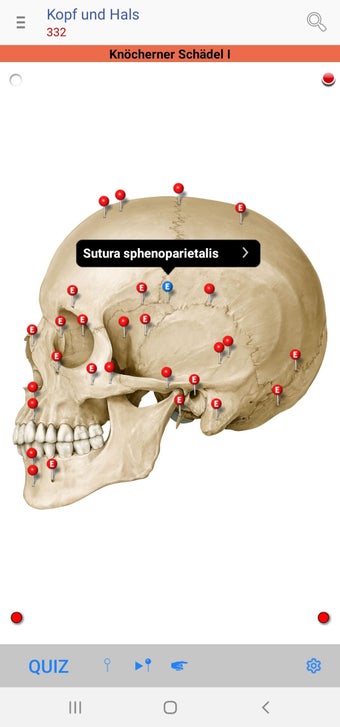

The app consists of different sections, each of which contains information about a specific part of the body. You will learn about the different organs, as well as the muscles, bones, and other important structures. You can test yourself with a unique quiz that consists of multiple-choice questions.

The app allows you to learn about the body in a simple and fun way, and to test yourself in a quick and easy way.